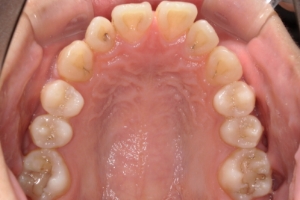

BEFORE

治療前

下の前歯が上あごの歯ぐきに当たるほど噛み合わせが深く、そのことが原因で上顎歯列の正中にすき間(正中離開)が生じていました。部分矯正ですき間を無理やり閉じても、噛み合わせが深いままでは治療後の再発リスクが高くなります。そのため全体矯正で奥歯の噛み合わせを整え、噛み合わせを浅くしつつ前歯を並べました。正中離開は戻りやすい傾向があるので、再発を防ぐため固定式リテーナーを推奨しています。